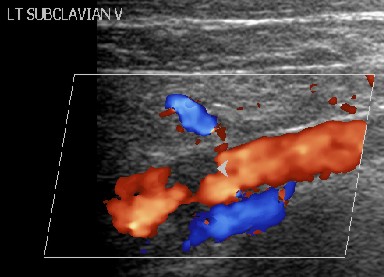

A 30-year-old man presented to our outpatient clinic with history of abdominal distention without pedal edema for the past 3 months. He also had deep boring epigastric pain and vomiting for 2 months. He had noticed low grade fever and anorexia for last 15 days. He had been consuming alcohol (100 g/day) for last 5 years (last drink 3 months back). Examination revealed pallor, facial puffiness, tachycardia, ascites and bilateral pleural effusion. His neck veins were engorged and hepatojugular reflex was absent. On investigation ascitic fluid was hemorrhagic with proteins 5.5 g/dL (reference range: 0-0.5 g/dL); white blood cells were 215 mm-3 (reference range: 0-5 mm-3; polymorphs 35% and lymphocytes 65% in a background of red blood cells). Ascitic fluid adenosine deaminase was 20 IU/mL (reference range: 0-35 IU/mL) and ascetic fluid amylase 58,840 IU/L (reference range: 0-100 IU/L). Pleural fluid was also hemorrhagic with protein 5.5 g/dL (reference range: 0-0.5 g/dL), white blood cells 80 mm-3 (polymorphs 50%, lymphocytes 50%) and adenosine deaminase was 35 IU /mL. 2D echo was normal. Serum amylase was 700 IU/L (reference range: 0-150 IU/L), serum lipase was 3,526 IU/L (reference range: 0-150 IU/L), and pleural fluid amylase was 5,748 IU/L (reference range: 0-50 IU/L). CT scan showed thromboses of bilateral subclavian and internal jugular vein, superior vena cava, infra renal inferior vena cava, a segment of suprarenal and infrahepatic inferior vena cava and right common iliac vein and patent splanchnic veins (Figures 1-5). Color Doppler abdomen showed normal portal vein of 10 mm diameter with hepatopetal flow, normal retrohepatic inferior vena cava with hepatopetal flow, while rest of inferior vena cava was thrombosed; all three hepatic veins well visualized with normal flow (Figure 6). MRCP revealed acute inflammation with underlying chronic pancreatitis with stricture at junction of head and body with intraductal calculi with leak at head and body junction and multiple loculated intra abdominal collections. The prothrombotic work up, including factor V Leiden, JAK 2 mutation, homocysteine, antiphospholipid antibody, protein C and S, and antithrombin III, was negative. Thus, a diagnosis of chronic pancreatitis with pancreatic ascites and pleural effusion with multiple extrasplanchnic thromboses due to pancreatitis was made. Patient was managed conservatively with intravenous heparin, initially continuous infusion of 1,000 units/hour and later on oral anticoagulants. ERCP with pancreatic sphincterotomy was done and a 5Fr x 10 cm stent was placed. Patient symptomatically improved with complete disappearance of ascites. His repeat color Doppler showed partial recanalization of superior vena cava, internal jugular vein and subclavian veins (Figure 7).

Figure 7. Post anticoagulation therapy status color Doppler shows significant reduction in size of thrombus in left subclavian vein. |